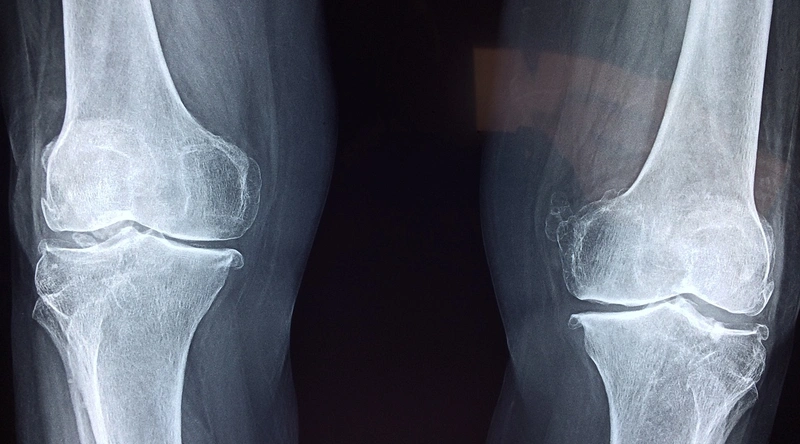

무릎이 아플 때 고려해야 할 여러 가지 원인이 있습니다. 일반적으로 관절염, 외상, 염증성 질환 등이 주요 원인으로 손꼽힙니다. 특히 관절염은 중년 이상에서 많이 발생하며, 무릎의 연골이 마모되어 발생하는 경우가 많습니다. 이 외에도 슬개대퇴 증후군, 통풍, 그리고 외상으로 인한 인대 손상 등이 무릎 통증의 원인이 될 수 있습니다.

퇴행성 질환 중 가장 흔한 것이 바로 골관절염입니다. 이 질환은 뼈와 뼈 사이의 연골이 닳아 없어져 통증을 유발하는데, 주로 중년 이상의 사람들에게 많이 발생합니다. 특히, 운동 후 통증이 심해지는 경우가 많아 운동을 피하게 되면 더욱 악화될 수 있습니다.